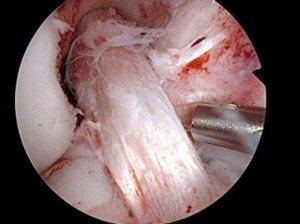

Graft being passed across knee joint

ACL Graft in Place